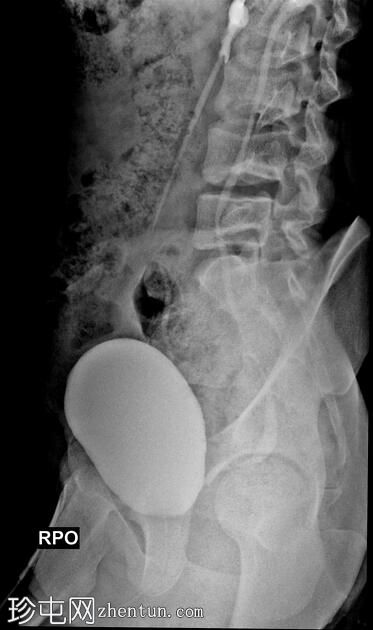

斜位

排尿性膀胱尿道造影显示尿液反流至

肾脏

,伴有输尿管和肾盂肾盏系统轻度扩张。

还观察到排尿后残余尿。

本病例描述了一例有复发性尿路感染病史的儿童,其双侧3级膀胱输尿管反流。